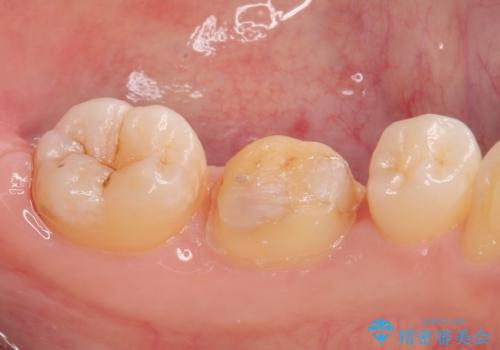

拡大鏡視野下で、金属の詰め物(メタルインレー)、虫歯の除去を行い、オールセラミッククラウンに適した形に整えました。

仮歯の状態で1週間ほど過ごしてもらい、しみる症状も改善されたので

歯と歯茎の間に圧排糸と言われる糸を入れてシリコーン印象材にて型どりをしました。